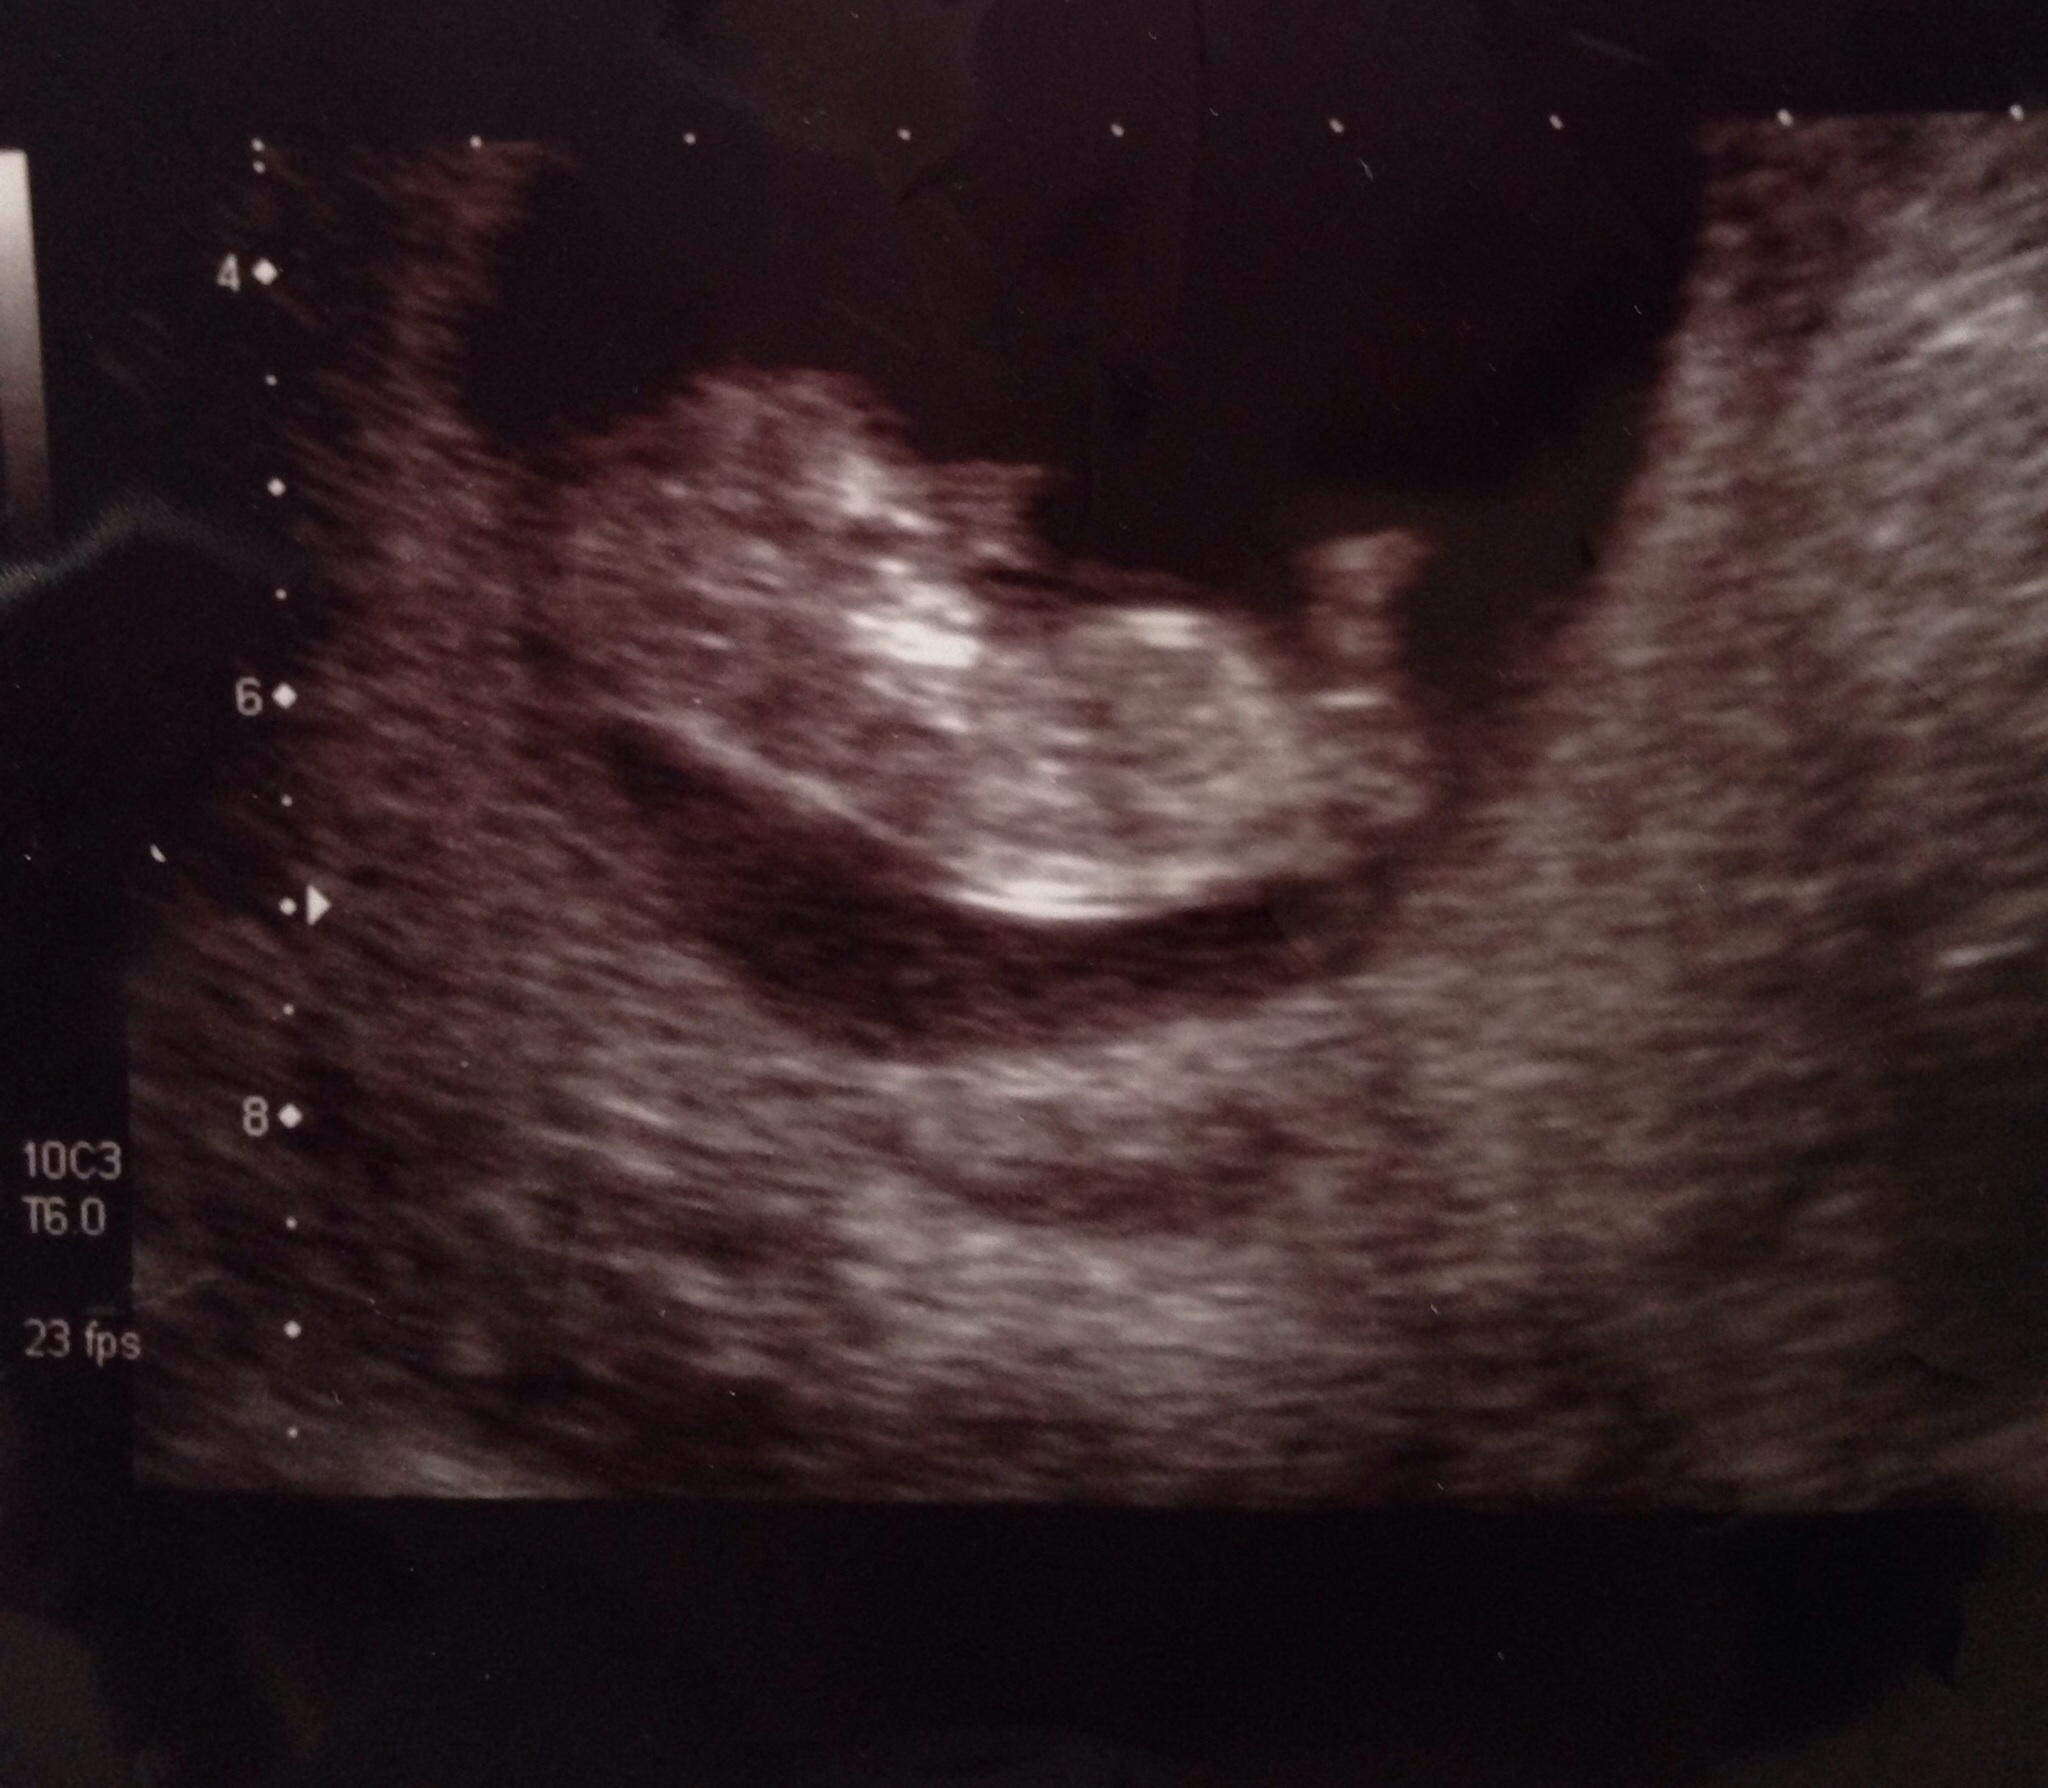

I'm not sure if this is in the right place or not but I was wonderingAttachment 20580Attachment 20580 if anyone could guess I am 11+1

Thank you. X

Too early :)

Yah way too early! Both genders look like this til after 12 weeks!

Too early